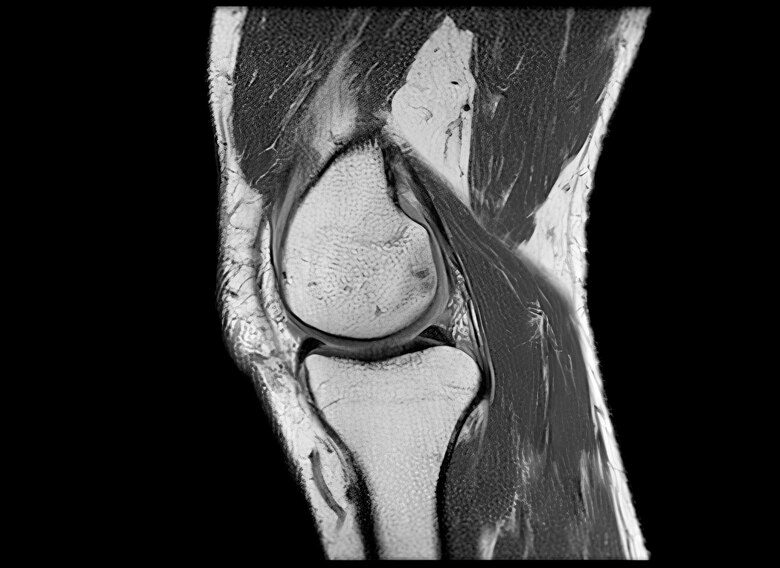

“La rodilla es una de las articulaciones más complejas de todo el cuerpo”, le dice a la BBC Anikar Chhabra, un cirujano ortopédico especializado en medicina deportiva de la Clínica Mayo en Phoenix, Estados Unidos.

Nuestras rodillas dependen especialmente de cuatro grupos de músculos que las rodean: los isquiotibiales, los de los glúteos, los cuádriceps y los músculos de la pantorrilla.

Esos grupos de músculos le permiten estabilidad y le dan la capacidad de absorción para poder funcionar.

Las investigaciones muestran que el estiramiento de ese grupo de músculos a través del ejercicio puede evitar la degeneración del cartílago en la rodilla, que es lo que luego puede conducir a una osteoartritis.